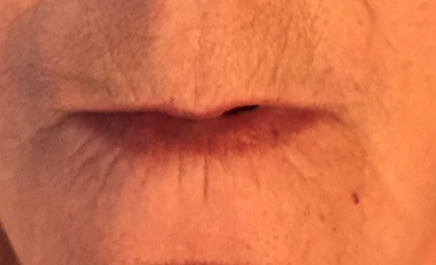

Prótesis fija maxilar con carga inmediata

Rehabilitación maxilar con exodoncias, regularización del proceso alveolar e implantes inmediatos.

La prótesis fija definitiva se ha confeccionado en cerámica.

Prótesis fija maxilar con carga inmediata

Foto de las rx de control, con la carga inmediata a la izquierda y con la prótesis definitiva a la derecha.

Prótesis fija maxilar con carga inmediata

Paciente que acude por fracaso de los dientes del maxilar superior por enfermedad periodontal

TRATAMIENTO en una sola fase: exodoncias, colocación de 8 implantes y dientes fijos en el día (carga inmediata). Prótesis definitiva de metal-porcelana